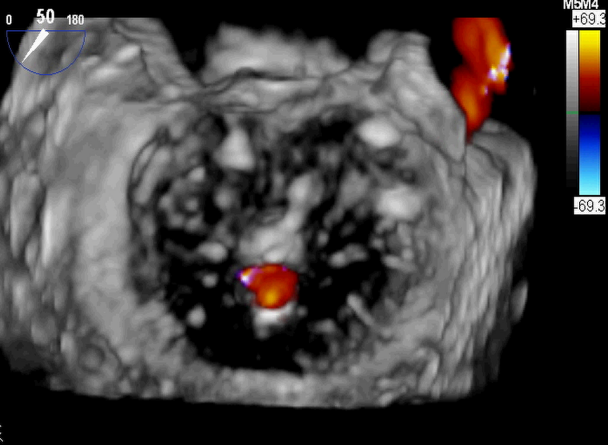

患者术前TEE提示重度功能性二尖瓣反流,反流位于A2/P2,瓣膜活动度可,后瓣较短,手术难度较高(图1)。手术采用经典股静脉房间隔途径,房间隔穿刺后植入24F导引导管及二尖瓣夹输送系统,在TEE引导下准确植入一枚二尖瓣夹,瓣膜夹位置稳定。瓣膜夹植入后反流明显减轻至轻度(图2),二尖瓣跨瓣平均压力阶差2mmHg,双孔化形成,遂移除输送系统。

图2:植入一枚瓣膜夹之后二尖瓣反流明显减轻